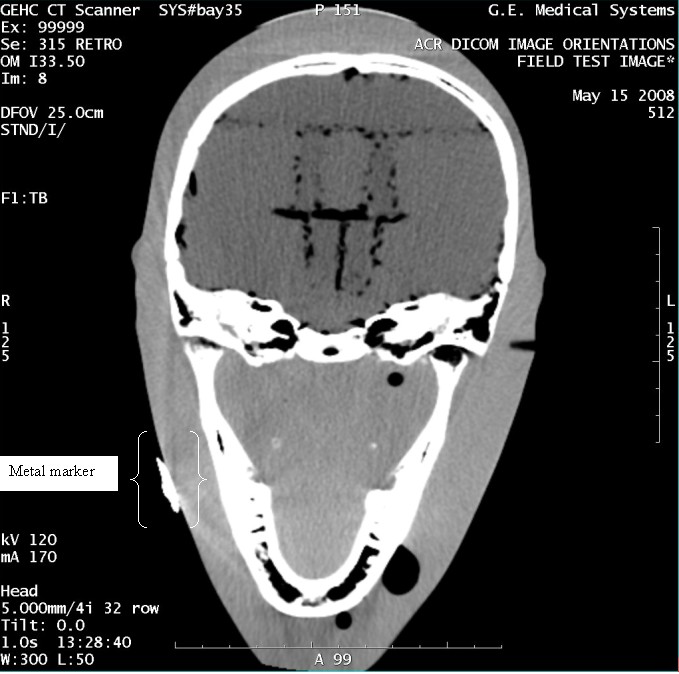

- With the support of the site personnel, examine the images sent

to the Review Station (i.e., 12 series, each with 1 image) and compare

their orientation to the images in this document.

- Each image contains a metal marker on the phantom's right cheek.

- Each image in this document contains a description of the expected

orientation of the metal marker (i.e. to prove Left and Right) as

well as the Posterior and Anterior orientation description.note:

The sample images included in this document use “R”, “L”, “P”, and “A” for “Right”, “Left”, “Posterior” and “Anterior” orientation. The Hospital Review Station may use a different style of annotation. The style used is not relevant to this procedure.

- Each image in this document has sufficient space to store the observed results for up to 4 Review Stations.

- Enter ‘Y’ in the space to indicate the observed result matches the expected.

- Enter ‘N’ in the space to indicate the observed result does not match the expected.

- Enter “NA” in the space if a column is not being used.

- Repeat for each destination.

Figure 4. Exam 99999, Series 315